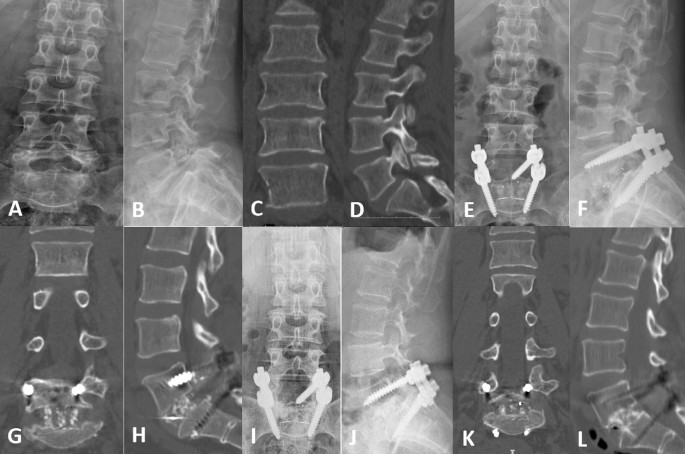

We present two representative cases: PMMA-PS (Fig. 2) and CPS (Fig. 3). The patients received good follow-up, including imaging and clinical evaluations.

Radiological images of a representative case with PMMA-PS. (A–L) A 62-year-old osteoporotic male with isthmic spondylolisthesis in the L4/L5 segments. (A–D) Preoperative X-rays and CT showed forward slip of the L4 vertebra and L4 spondylolysis. (E–H) Postoperative X-ray and CT showed that the internal fixation position was good and that the bone cement was in the vertebrae. (I–L) Postoperative X-ray and CT at 36 months after fusion surgery showed that the internal fixation device did not loosen or break, the vertebra did not show slippage, the intervertebral fusion was good, the bone cement was well filled, and there was no obvious cement leakage.

Radiological images of a representative case with CPS. (A–L) A 61-year-old osteoporotic female with isthmic spondylolisthesis in the L5/S1 segments. (A–D) Preoperative X-rays and CT showed forward slip of the L5 vertebra and L5 spondylolysis. (E–H) Postoperative X-rays and CT showed that the internal fixation position was good and that the L5 vertebra was well reset. (I–L) Postoperative X-ray and CT at 24 months after fusion surgery showed that the internal fixation device did not loosen or break, the vertebra did not show slippage, and the intervertebral fusion was good.